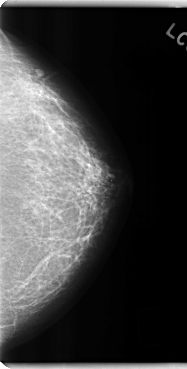

C_0201_1.LEFT_MLO

C_0201_1.LEFT_CC

LEFT_MLO LINES 4744 PIXELS_PER_LINE 2232 BITS_PER_PIXEL 12 RESOLUTION 50 NON_OVERLAY